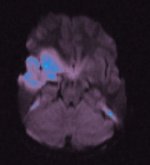

Aber es lag eine Einblutung in der Carotis Interna

(Carotis Dissektion) vor, welche nicht zu erklären war.

CT meines Schädels;

sichtbarer Schlaganfall in der rechten Hirnhälfte. |